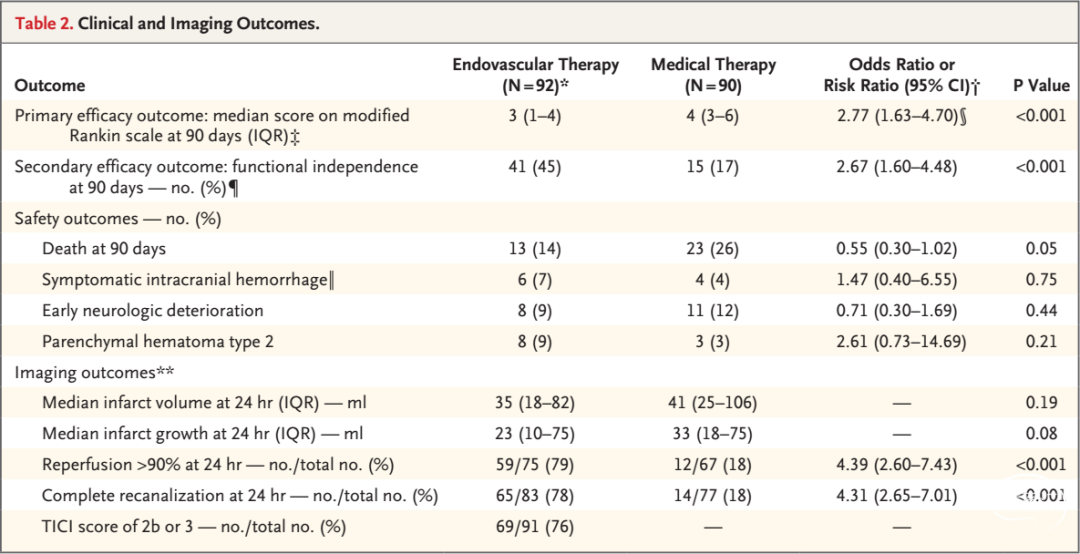

2018年1月24日,美国心脏协会/美国卒中协会(AHA/ASA)发布的《2018急性缺血性卒中患者早期管理指南》为临床医生处理成年急性缺血性卒中提供了一个最新最全面的建议。

大动脉闭塞性卒中采用以机械取栓为主的动脉内多模式治疗方法较传统的静脉溶栓能显著提高血管再通率,明显改善远期预后,且并不增加颅内出血率及病死率。

2015年以来连续发表的6项RCT研究以及DAWN、DEFUSE 3研究证实,对伴有大血管闭塞的急性缺血性卒中患者行血管内介入治疗可显著改善患者90天临床预后。

《2018急性缺血性卒中患者早期管理指南》以最高等级的证据推荐了6~16小时的取栓治疗,以B-R级别的证据推荐了6~24小时的取栓治疗。